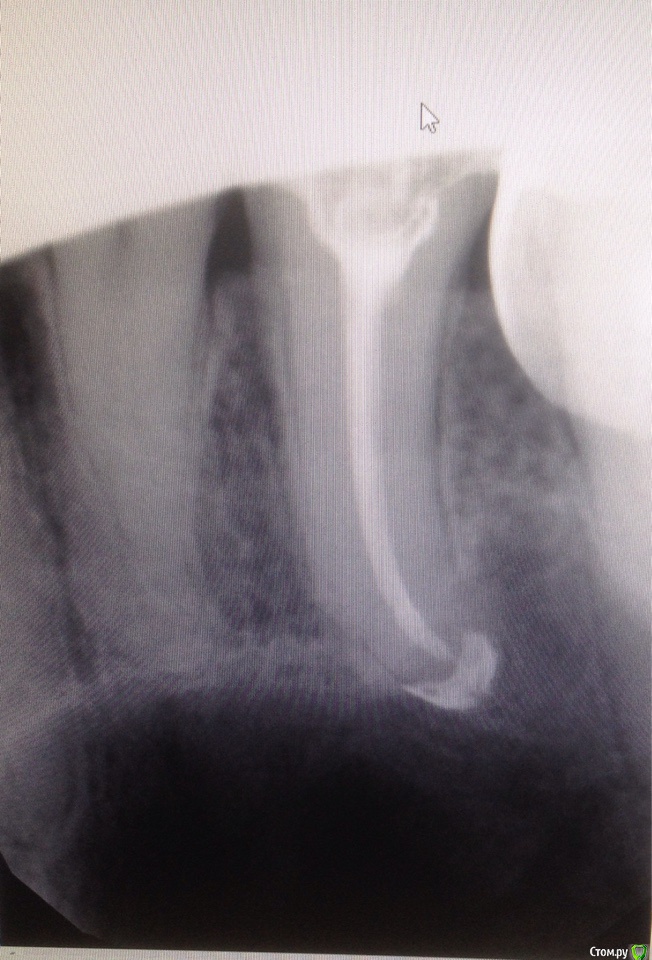

Евгения 66 Опубликовано 23 января, 2015 Автор Поделиться Опубликовано 23 января, 2015 Вот снимок зуба супруга. Это 15. Канал запломбирован 09.01. Ощущения такие же,как у меня-больно при прстукивании. И также виден выход материала за пределы корня. Как-то беспокойно. Прокомментируйте,пожалуйста.Большое спасибо! Ссылка на комментарий

Евгения 66 Опубликовано 25 января, 2015 Автор Поделиться Опубликовано 25 января, 2015 Чтобы ответить на Ваш вопрос нужны рентген снимки всех этапов лечения Большое спасибо за ответ! Только никаких этапов не было. В Карте этот зуб записан со знаком R+,то есть,как я понимаю,периодонтит. В одно посещение был запломбирован канал и поставлена временная пломба,как я понимаю,в зуб. На следующем посещении-21.03.мы спросили,почему пломба временная ( думали,что заложено лекарство ). Док.ответила,что лекарства там нет,а почему временная и что она собирается с этим зубом делать дальше,так и не объяснила. "Выброс" то ли пломбировочного материала на снимке,то ли кальция ( как она мне объясняла с моими зубами ),мы увидели уже только дома и только 22.01. На следующий визит в клинику едем завтра. Прилагаю фото Карты,где записано лечение этого зуба. Нет.Здесь,похоже,это не получится. Не знаю,как открыть окно " Расширенная форма ". Сейчас попробую вернуться в тему. Ссылка на комментарий

Евгения 66 Опубликовано 25 января, 2015 Автор Поделиться Опубликовано 25 января, 2015 А,вот нашла. Прилагаю и заранее очень благодарю за ответ. Ссылка на комментарий